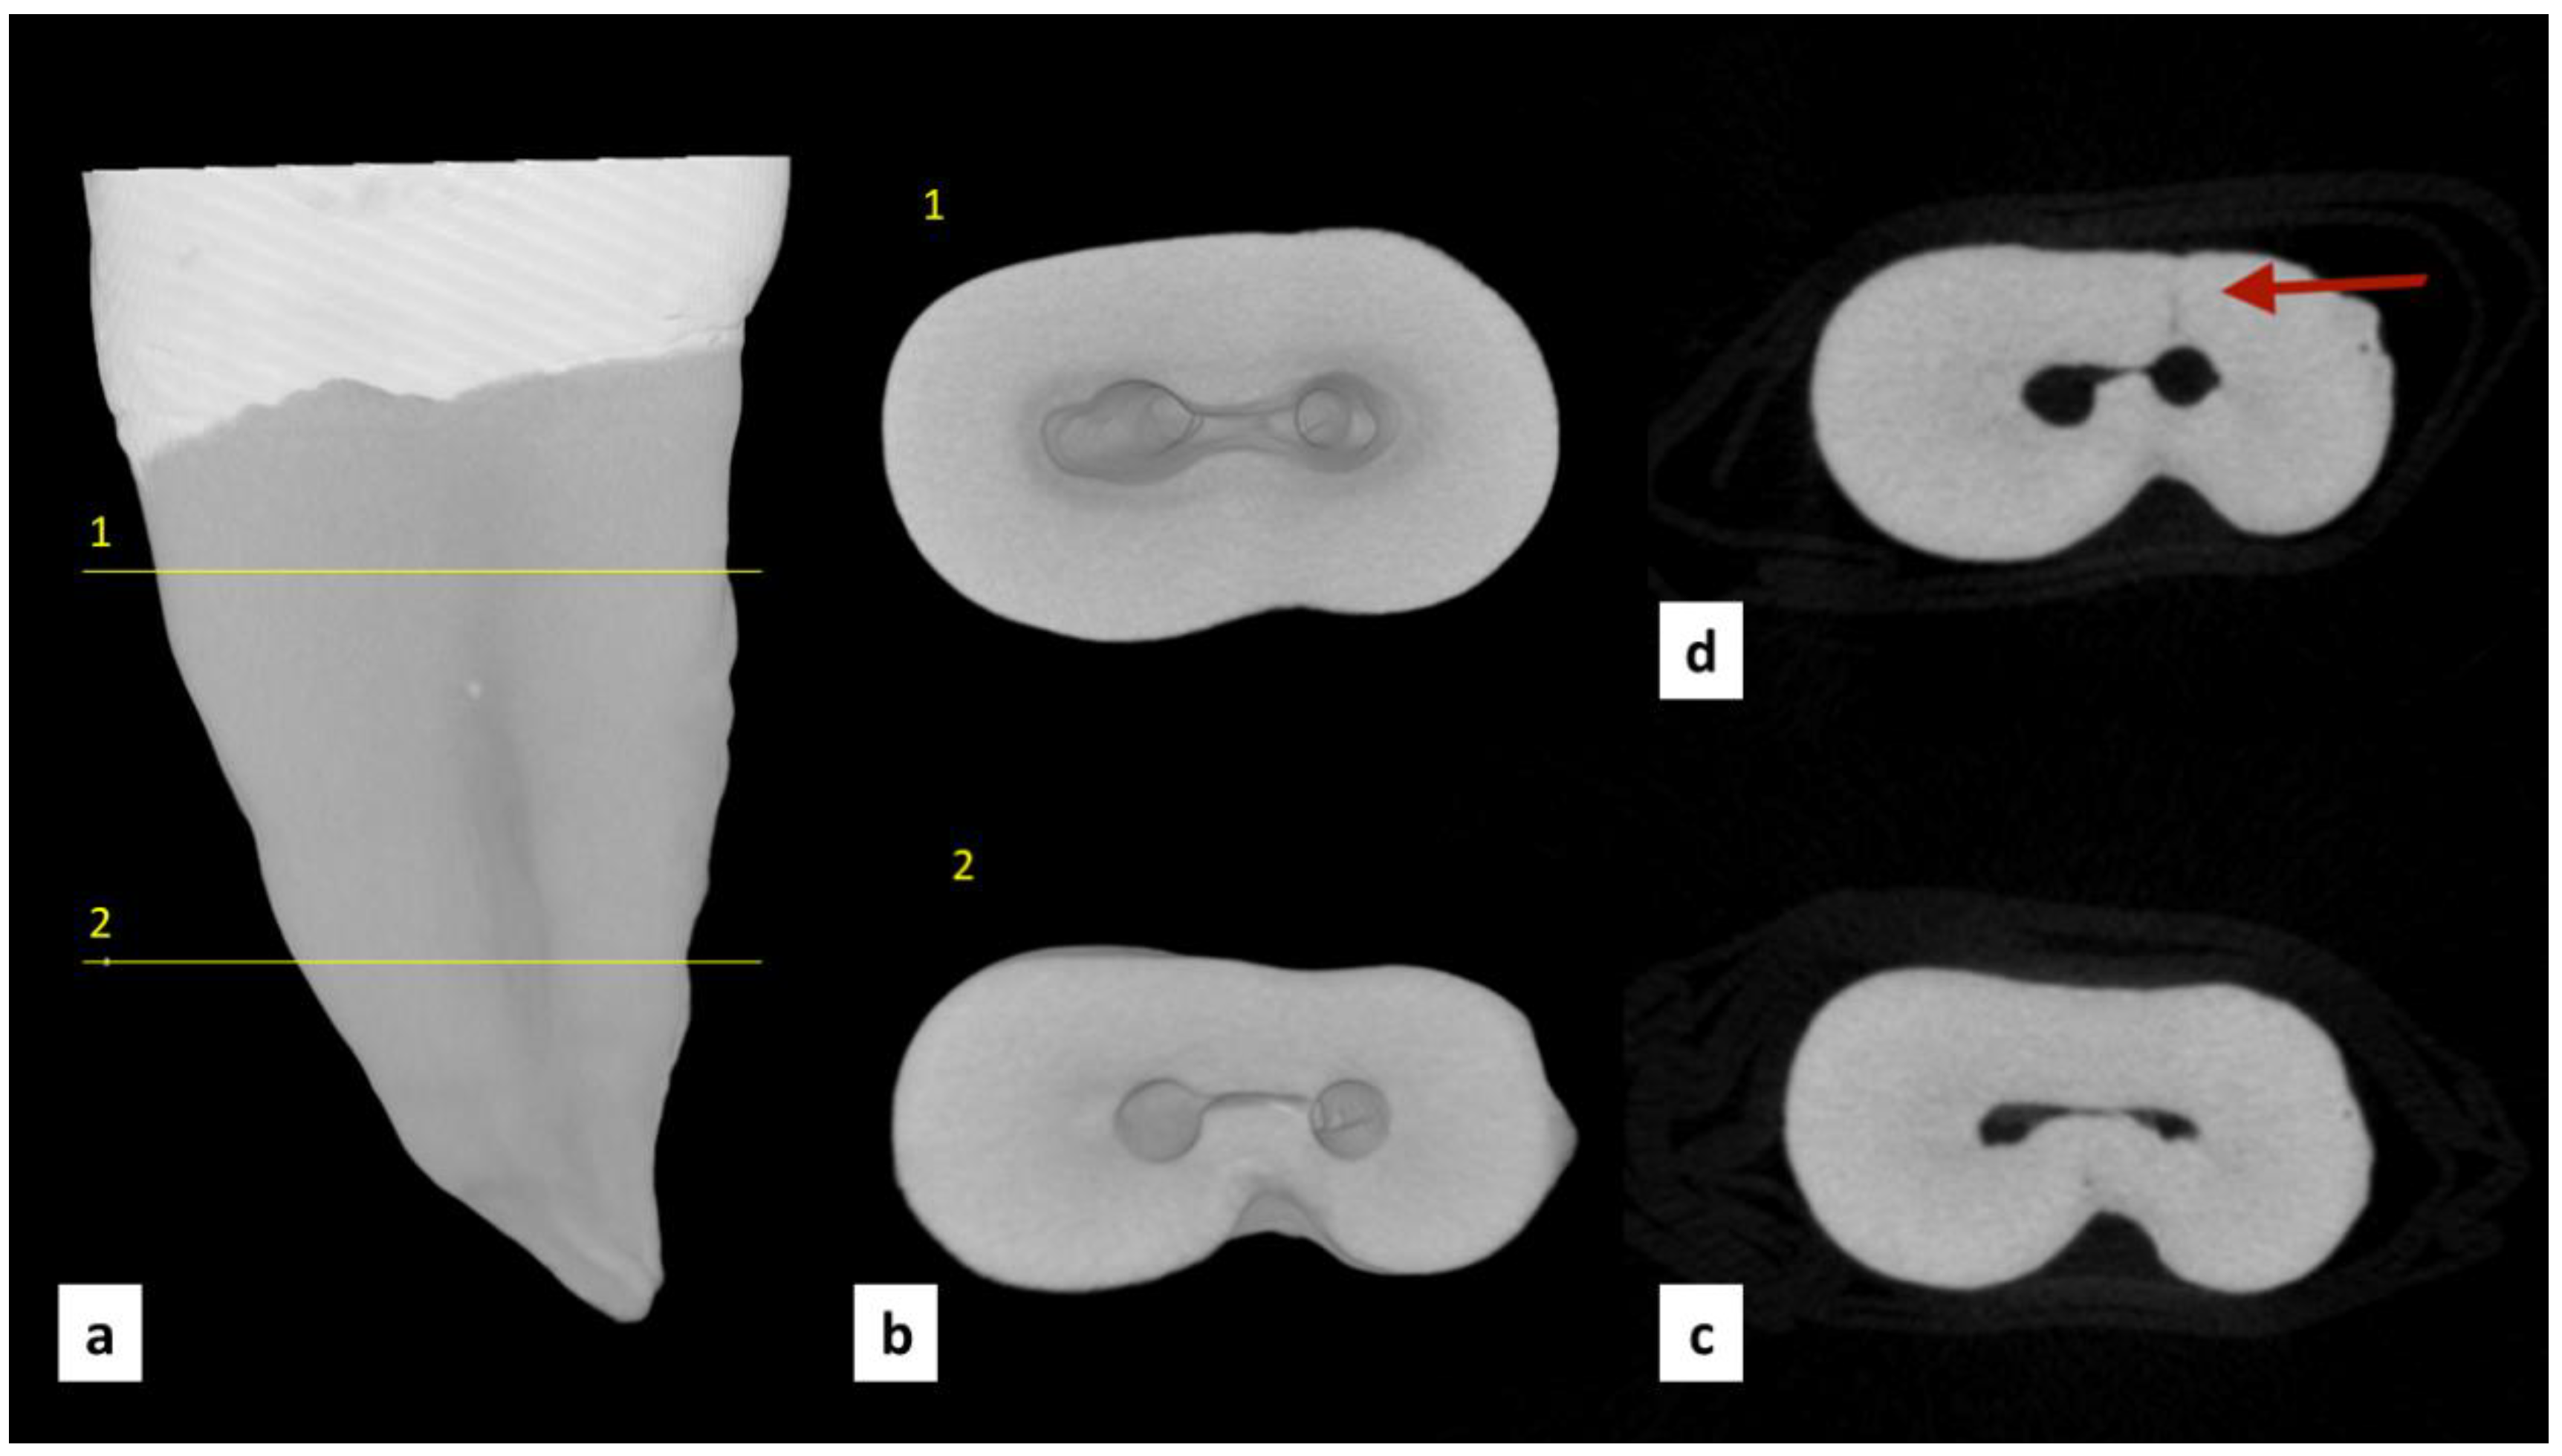

2.2. MicroCT Scanning

2.4. Sectioning and Microscope Analysis